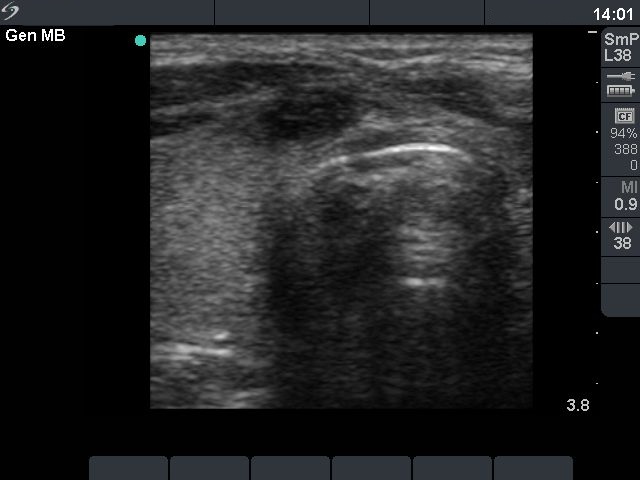

Three days after the fourth session (second row):

Clinical presentation: 3 days after the fourth session of the ethanol treatment: the cyst became more enlarged and painful. The body temperature rose to 38.2 C, the erythrocyte sedimentation rate was 50 mm/H.

Ultrasonography: the size of the nodule was 30x25x34 mm, and another hyperechogenic lesion was found dorsal to the treated lesion.

Steroid administration resulted in a prompt amelioration of the clinical symptoms. The steroid was given for 6 weeks in a decreasing dose.